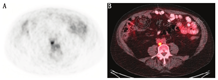

对于前列腺外复发病灶的检测,一项研究报道18F-fluciclovine PET显像的诊断灵敏度、特异性、PPV和准确性分别为55.0%、96.7%、95.7%和72.9%(未考虑PSA水平或倍增时间)[29]。一项纳入596例患者的大型多中心临床研究同样得出较高水平的PPV,为92.3%[27]。一项纳入53例患者的研究将18F-fluciclovine PET/CT和单纯CT进行了比较,结果显示18F-fluciclovine PET/CT检出前列腺外复发患者的真阳性率为29%,而CT仅为7%;另外,18F-fluciclovine PET/CT检出转移淋巴结的最小短径为0.4 cm,CT为0.9 cm[25]。综上,18F-fluciclovine PET/CT对前列腺外复发病灶的检出效能明显优于CT (图2)。另有研究表明,同一患者多次18F-fluciclovine PET/CT显像本底平均标准摄取值(mean standardized uptake value, SUVmean)差异小于20%,未经治疗的肿瘤病灶摄取随时间推移增高或保持稳定,复测重复性较好,因此可应用18F-fluciclovine PET检查对患者随访,进行疾病评估[30]。